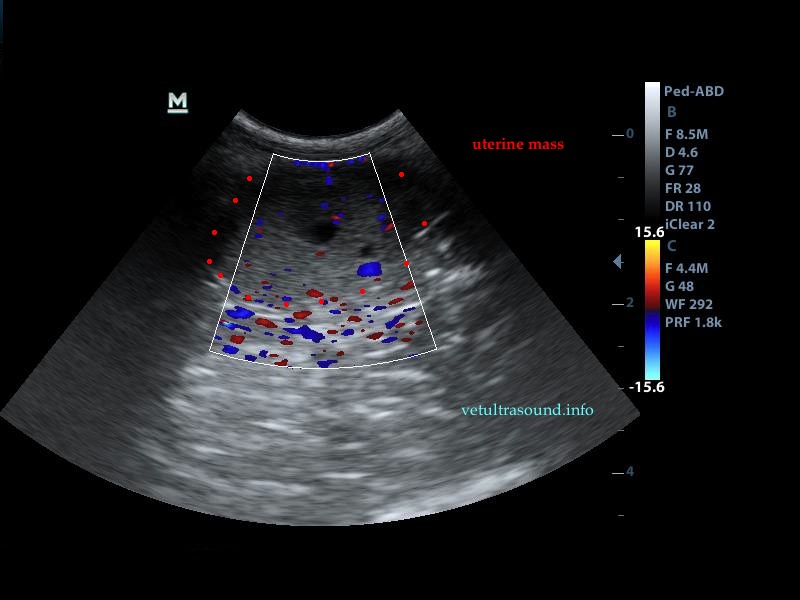

Findings: There were three uterine masses with hypoechoic center. They were located one on the left uterine horn and two on the right. No abdominal fluid was noted. The rest of the abdominal organs were normal.

Diagnose: Uterine adenocarcinoma. The owners proceeded to ovariohysterectomy.